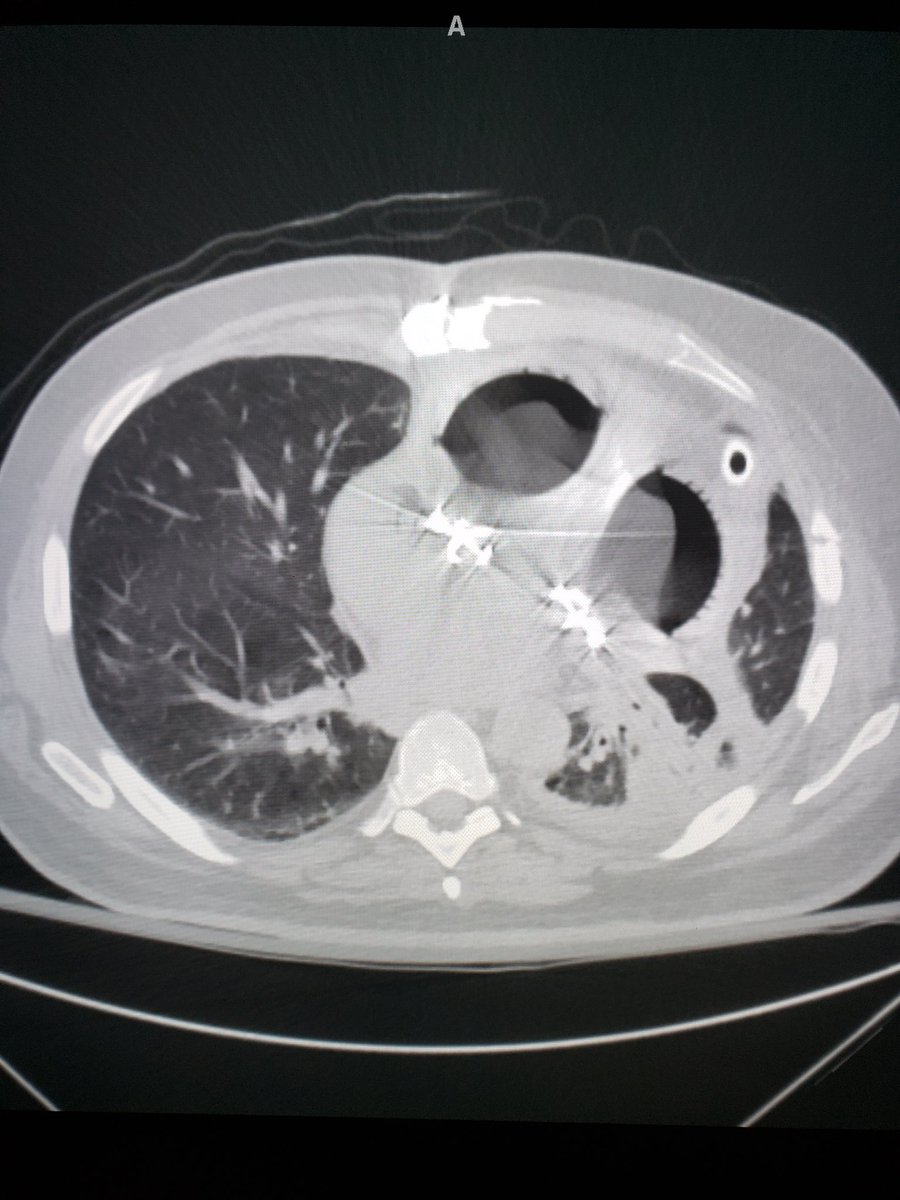

Not something you see every day - this

#patient has a total artificial heart. Pneumatic ventricles are quite striking to see on CT, especially as a#RadRes on call!#Radiology#ChestRad#FOAMradpic.twitter.com/kZ4BQUiGym